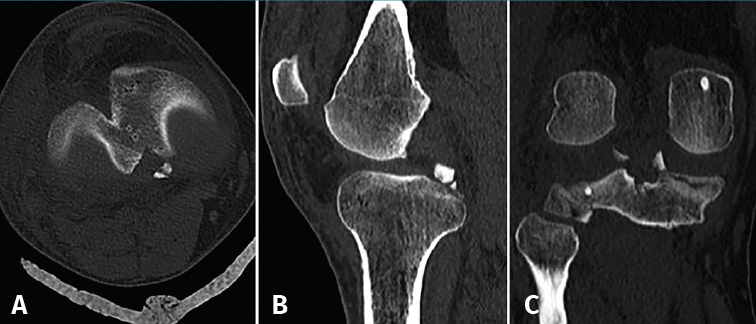

The computed tomography (CT) study evidenced a fracture of the posterior region of the internal tibial plateau with millimetric collapse and sub-centimetre avulsed fragments located immediately medial to the posterior cruciate ligament (PCL), together with a small fracture in the posterior cortical layer of the external tibial plateau without collapse, displacement or comminution (Figure 2).

Figure 2. The axial (A), sagittal (B) and coronal (C) computed tomography views show the avulsed bone fragments dependent upon the posterior root of the medial meniscus, near the insertion of the posterior cruciate ligament.